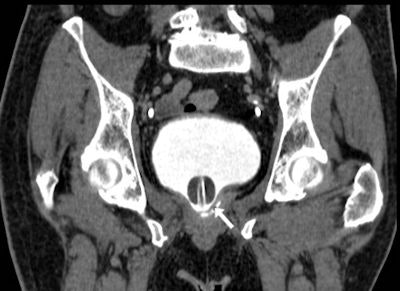

In their department, diluted iodinated CM used during MDCT cystography is prepared by removing 40 mL to 50 mL of normal saline from a 500-mL bag and injecting a similar amount of nonionic contrast agent (e.g., 350 mgI/mL iomeprol or 370 mgI/mL iopromide) into the same saline solution bag. The bag is then connected to standard tubing for intravenous infusions, filling the tube with diluted contrast to avoid instilling air in the bladder. With the patient supine on the CT scanner table, slow retrograde infusion is obtained by gravity.

The injected CM volume should not exceed 150 mL, according to the group. The volumetric MDCT acquisition at sufficient bladder distension is visualized with multiplanar image reformations at CT angiography window settings (width 600-900 level 150-300 Hounsfield Units) and by maximum intensity projection or 3D techniques. The only potential pitfall of this technique is the possible occlusion of a limited anastomotic dehiscence by the Foley catheter balloon, they added.